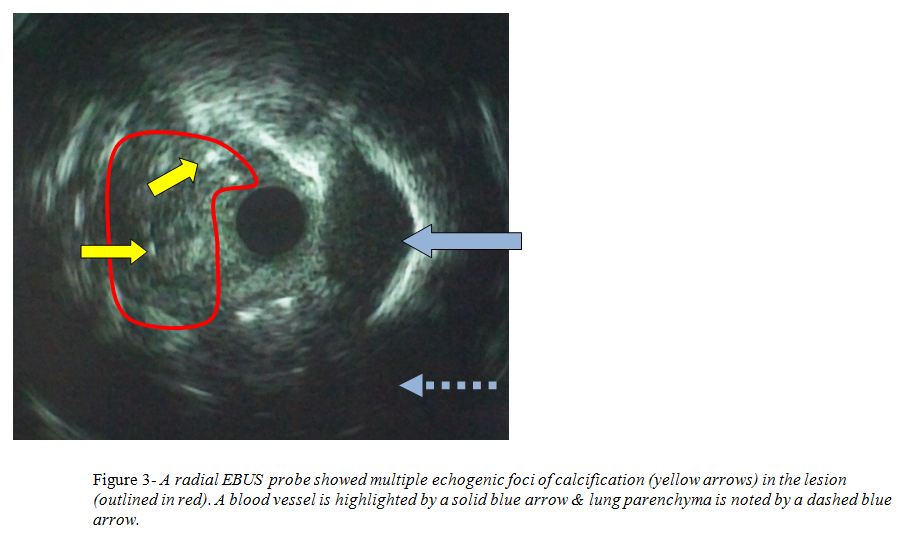

A flexible bronchoscopy was performed and a polypoid lesion was found occluding the orifice to the superior segment of the right lower lobe (Figure 2). A radial endobronchial ultrasound probe was used to further aid in the diagnosis of the lesion and it showed multiple echogenic foci of calcification (Figure 3). In order to diagnose the lesion and to restore patency of the airway an electrocautery snare was used to remove the lesion.